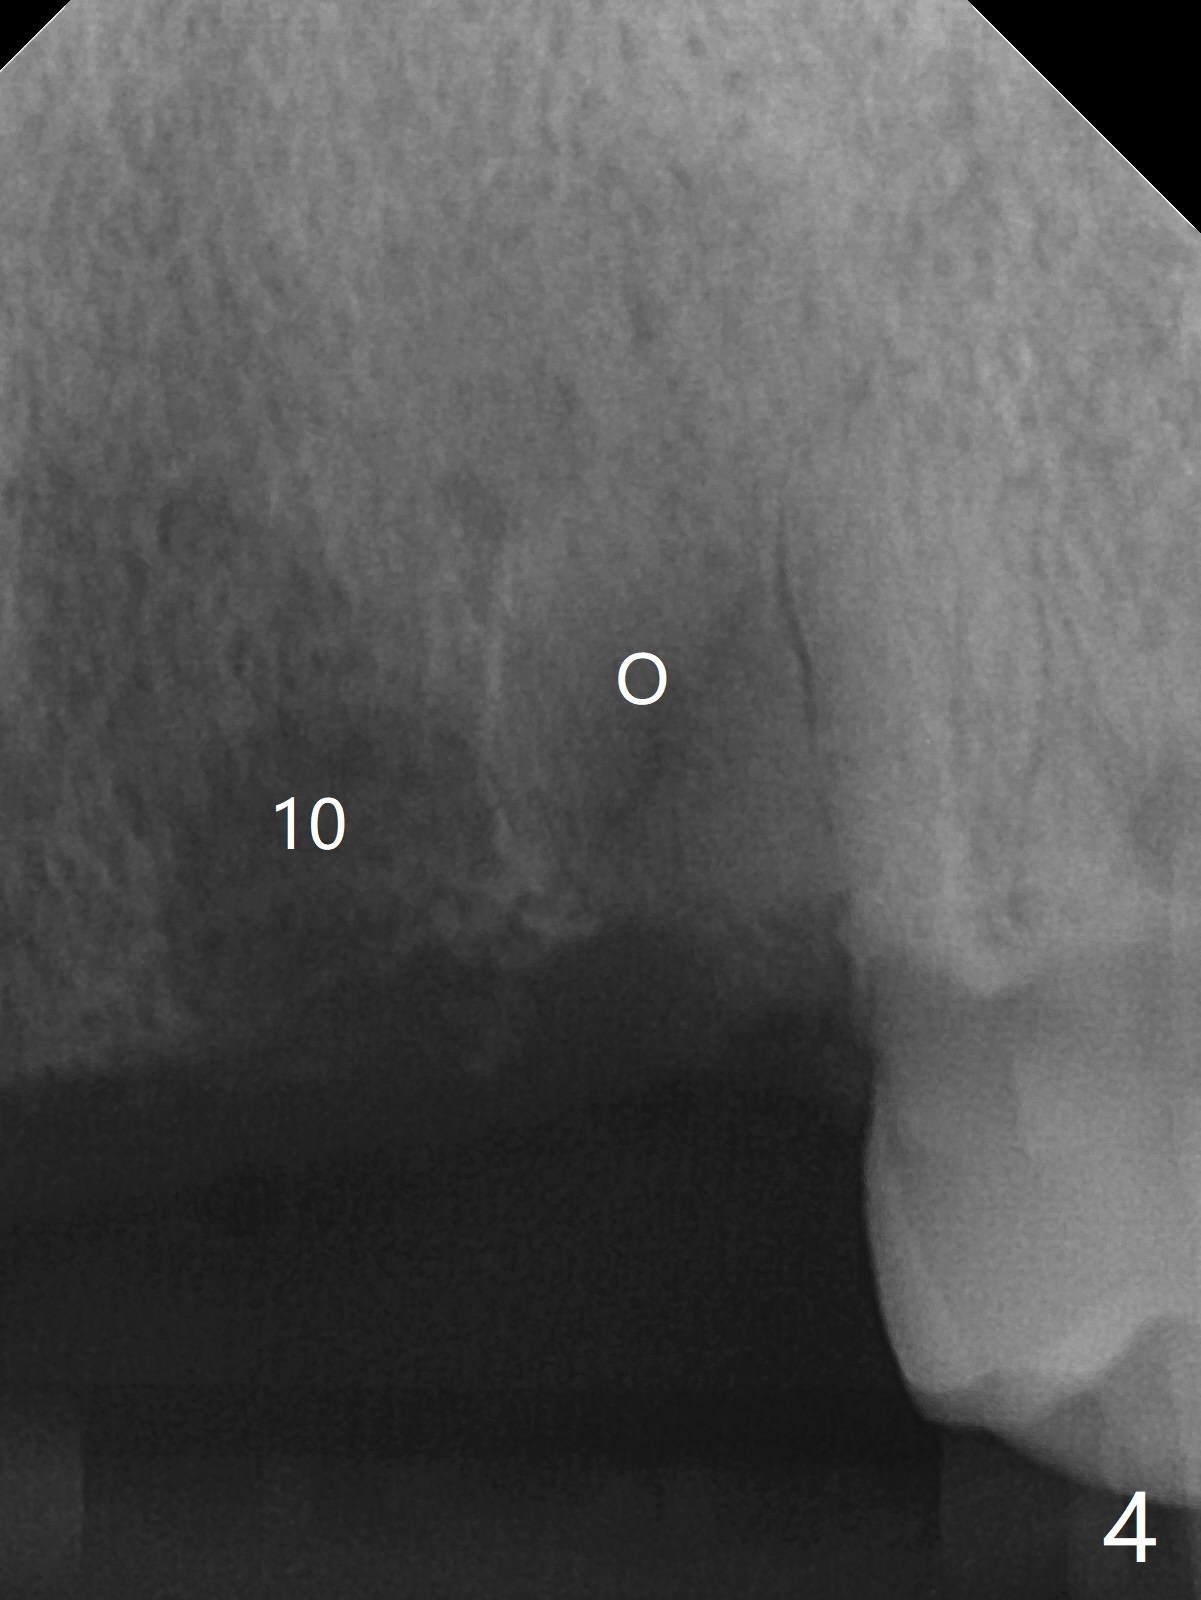

A 81-year-old man with upper and lower RPDs (Fig.1) requests extraction of the tooth #11 (Fig.2,3). After discussion, he agrees with socket preservation using Osteogen plug (Fig.4 O). The density at #11 is in fact higher than the neighboring healed socket (#10). Due to failure to transfer the flap to cover the socket and poor oral hygiene, the wound does not heal as well as expected 13 days postop (Fig.5).